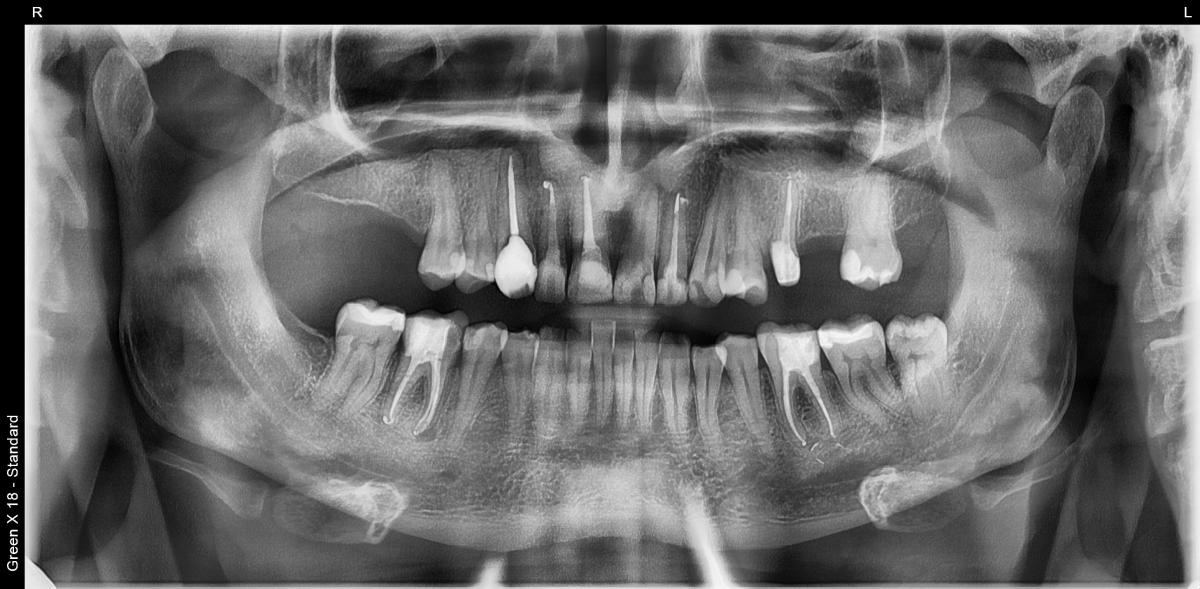

Делали 13 зуб, хронический периодонтит. Дистальная стенка ушла под десну. Делали эндо, врач почему-то решила сразу пломбировать каналы и сделать реставрацию композитом. Ничего не сказала, но на ОПТГ и КТ вот такая картина. Как будто трещина, да? Включая и материал в канале тоже - фрагментация какая-то...

Перелом?